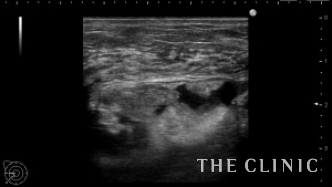

術前のエコーです。

乳腺下に充実性のしこりがあります。右はカプセル内ですがしこりは移動しませんでした。左はカプセル内を広範囲に移動します。他にも1.5㎝の小さなしこりもありこれも移動します。